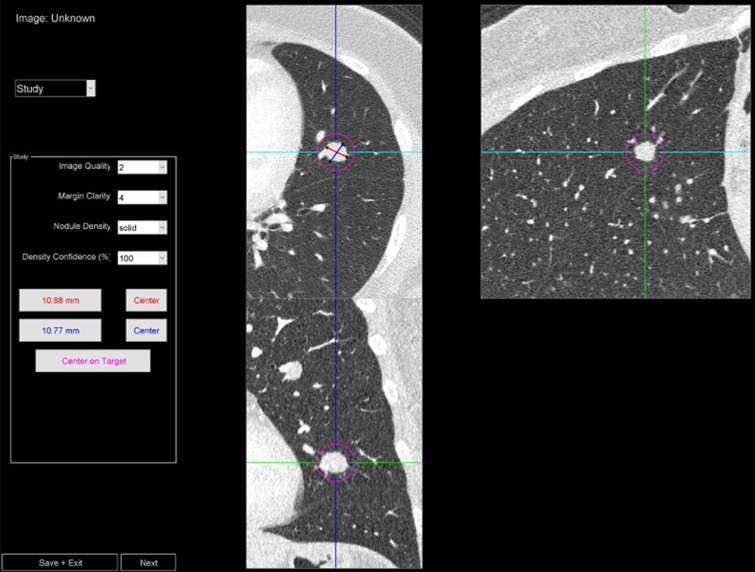

Material and methods: 104 non-contrast chest UHRCT scans (mean age of 66 years, 57 females) with pulmonary nodules were retrospectively collected (February-November 2022), and corresponding normal-resolution (NR) reconstructions were synthesized using a validated algorithm. Five blinded radiologists scored the following for each localized nodule in the ultra-high-resolution (UHR) and NR datasets: Margin clarity (5-point Likert scale), image quality "IQ" (3-point), density confidence (0-100%), and size (long/short axes). Image noise (voxel standard deviation) was calculated within the trachea. Differences between UHR and NR were tested using the Wilcoxon signed-rank test. Intrareader agreement was quantified with intraclass correlation coefficient (ICC), and ordinal association between margin clarity and IQ was quantified with Kendall's τ coefficient.

Abstract Image